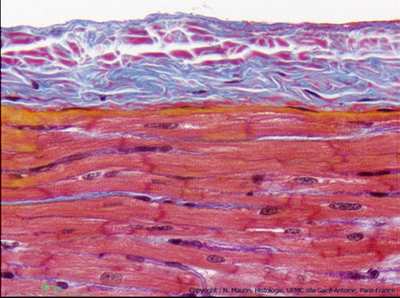

Regarde ici, l'endocarde est beaucoup plus fin (c'est parce que cette coupe n'a pas été réalisé au même endroit que celle présentée par le prof

)

Tu vois que cette coupe est colorée au HES => les fibres de collagène apparaissent orange

Il y a dont bien un tissu conjonctif très fin qui sépare myocarde et endocarde (épithélium).